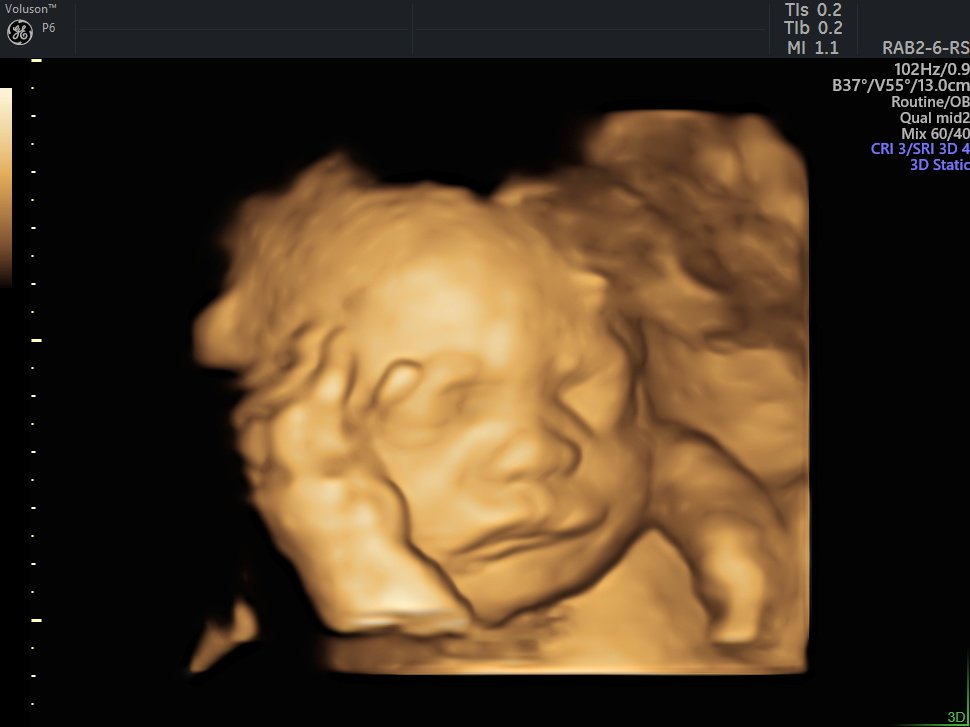

4 Boyutlu (Renkli) Ultrason ve Doppler Ultrasonografi

4 D Ultrasonografi